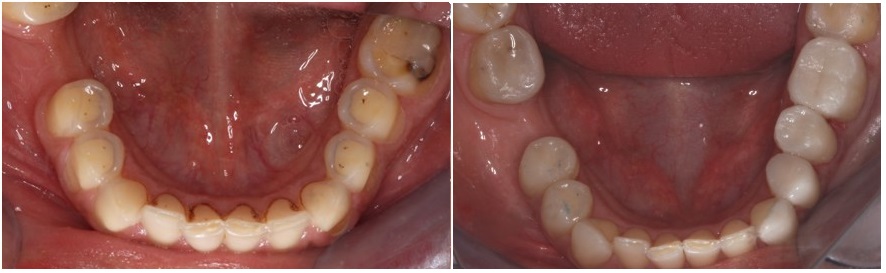

The following pictures present the occlusal surfaces of the maxillary and mandibuler teeth, before and after the cementation of our aditive restorations.

Most teeth had lost their enamel and a significant portion of dentin. Teeth had also lost their anatomical features while the height of the lower third of her face had decreased.

Old fillings were protruding over her teeth, ans some of the teeth were decayed.

Erosion had affected most of the maxillary and mandibular teeth.